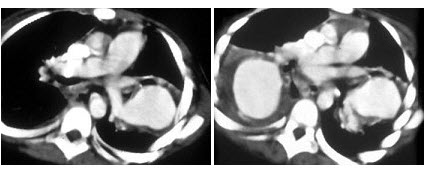

19、单项选择题

患者腹胀,盗汗,结合所示图像,最可能的诊断是()

A.淋巴瘤

B.肾癌

C.急性肾盂肾炎

D.肾结核

E.肾囊肿

20、单项选择题

女,67岁,进行性吞咽困难半年,X线及CT检查如图,最可能的诊断为()

A.食管癌

B.食管憩室

C.食管炎

D.食管良性狭窄

E.食管静脉曲张

21、单项选择题

患者50岁,可能性最小的诊断是()

A.骨纤维结构不良

B.转移瘤

C.软骨肉瘤

D.骨髓瘤

E.以上都不是

22、多项选择题

男,54岁,左侧腰痛,伴间歇性血尿2个月余,结合所示图像,下列哪项描述正确()